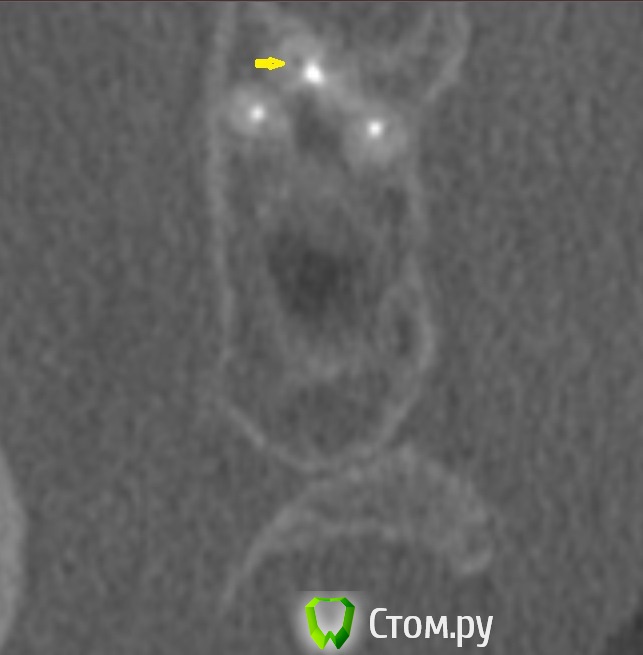

dr-krasnov Опубликовано 10 июня, 2014 Поделиться Опубликовано 10 июня, 2014 Добрый день. На томограмме ретенционная киста слева, одонтогенный синусит справа, замыкательная кортикальная пластина в области корня уже отсутствует. (желтые стрелки) С моей точки зрения необходимо эндоперелечивание причинного зуба. К лору можно сходить за рекомендациями по поводу ретенционной кисты. Обычно с ними ничего не делают, пока они не беспокоят. 1 Ссылка на комментарий

dr-krasnov Опубликовано 10 июня, 2014 Поделиться Опубликовано 10 июня, 2014 (изменено) Тэкс, посмотрел КТ. Претензий к лечению зуба не имею. 4й канал найти не удалось. То был ограниченный артефакт от запломбированного канала. Связи между этим зубом и реакцией слизистой скорее всего нет. Да и синусита нет. Изменения слизистой скорее имеют гиперпластическую природу. Источником исходных реакций послужили уже отсутствующие зубы. Архивные снимки расставили бы все точки над и. Несколько картинок: Небный на осях, можно придраться к незначительному расширению периодонтального пространства апикально, но я бы не стал http://s018.radikal.ru/i515/1406/b8/d712dd4f6158.jpg Дистальный щечный http://s020.radikal.ru/i710/1406/4f/990608ed482a.jpg Мезиальный щечный http://s018.radikal.ru/i518/1406/52/534d8d8534ec.jpg В общем, признаков периодонтита не вижу, рентгенологических показаний для резекции тоже.Я бы порекомендовал динамическое наблюдение. Изменено 10 июня, 2014 пользователем dr-krasnov 1 Ссылка на комментарий